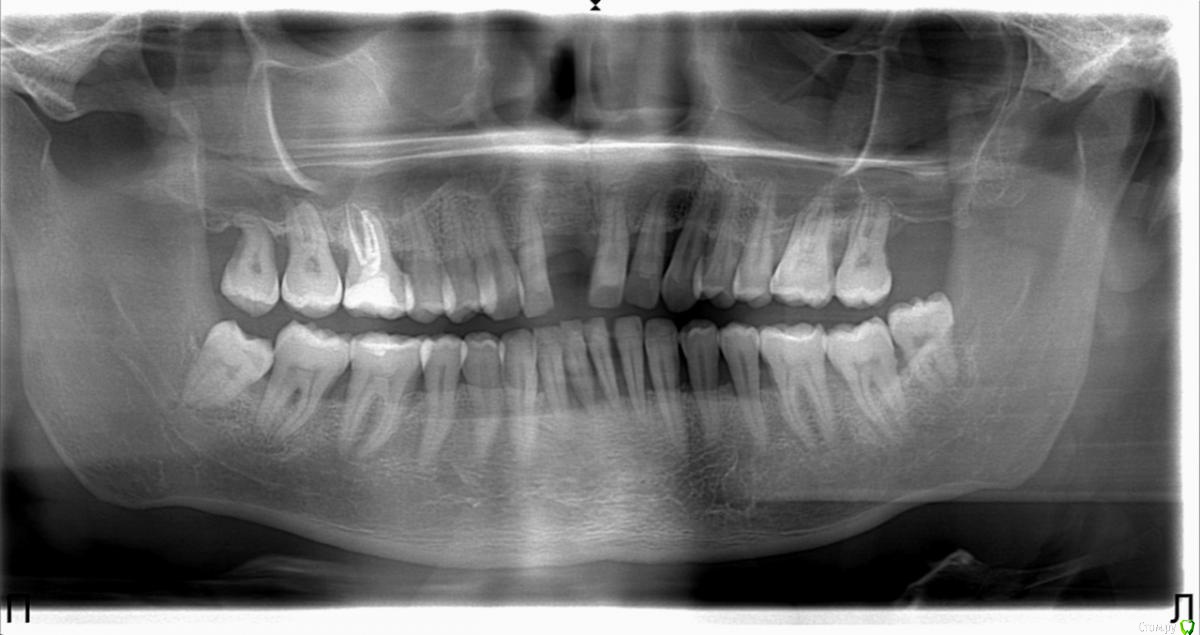

serg174 Опубликовано 14 января, 2020 Поделиться Опубликовано 14 января, 2020 Здравствуйте. Год назад потерял передний зуб, решил вставить имплант перед этим пролечить все проблемные зубы и сделать проф. чистку. Пролечили мне верхние 6 (верхнюю левую просто убрали кариес и запломбировали, верхнюю правую лечили, ставили лекарство на 2 дня с временной пломбой). Потом так получилось что пришлось сделать шинирование нижних передних зубов. После этого спустя примерно пол года над пролеченными зубами начали вспухать дёсна. Вообще меня сейчас беспокоит верхняя левая 6, она не болит НО десна над неё как бы припухшая (и отдаёт каким то жужжанием в область виска). Делал КТ височных костей, ничего серьёзного не нашли. Ссылка на комментарий

колесников Опубликовано 15 января, 2020 Поделиться Опубликовано 15 января, 2020 Здравствуйте! Верхнюю правую восьмерку удалить. Провести диагностику окклюзии. Проф гигиена и контроль через 3 мес. Делать проф гигиены не реже чем раз в 4-6мес. Использовать ирригатор и ёршики каждый день как доп средства гигиены. Пасты с антисептиками (типа эльгидиум). Внутрь Витаминотерапия (особенно С). Уезжать из Челябинска как можно скорее,эта местность ,вода и климат вредят вашим дёснам. 1 Ссылка на комментарий

red_butler Опубликовано 15 января, 2020 Поделиться Опубликовано 15 января, 2020 Все восьмые зубы удалять Ссылка на комментарий